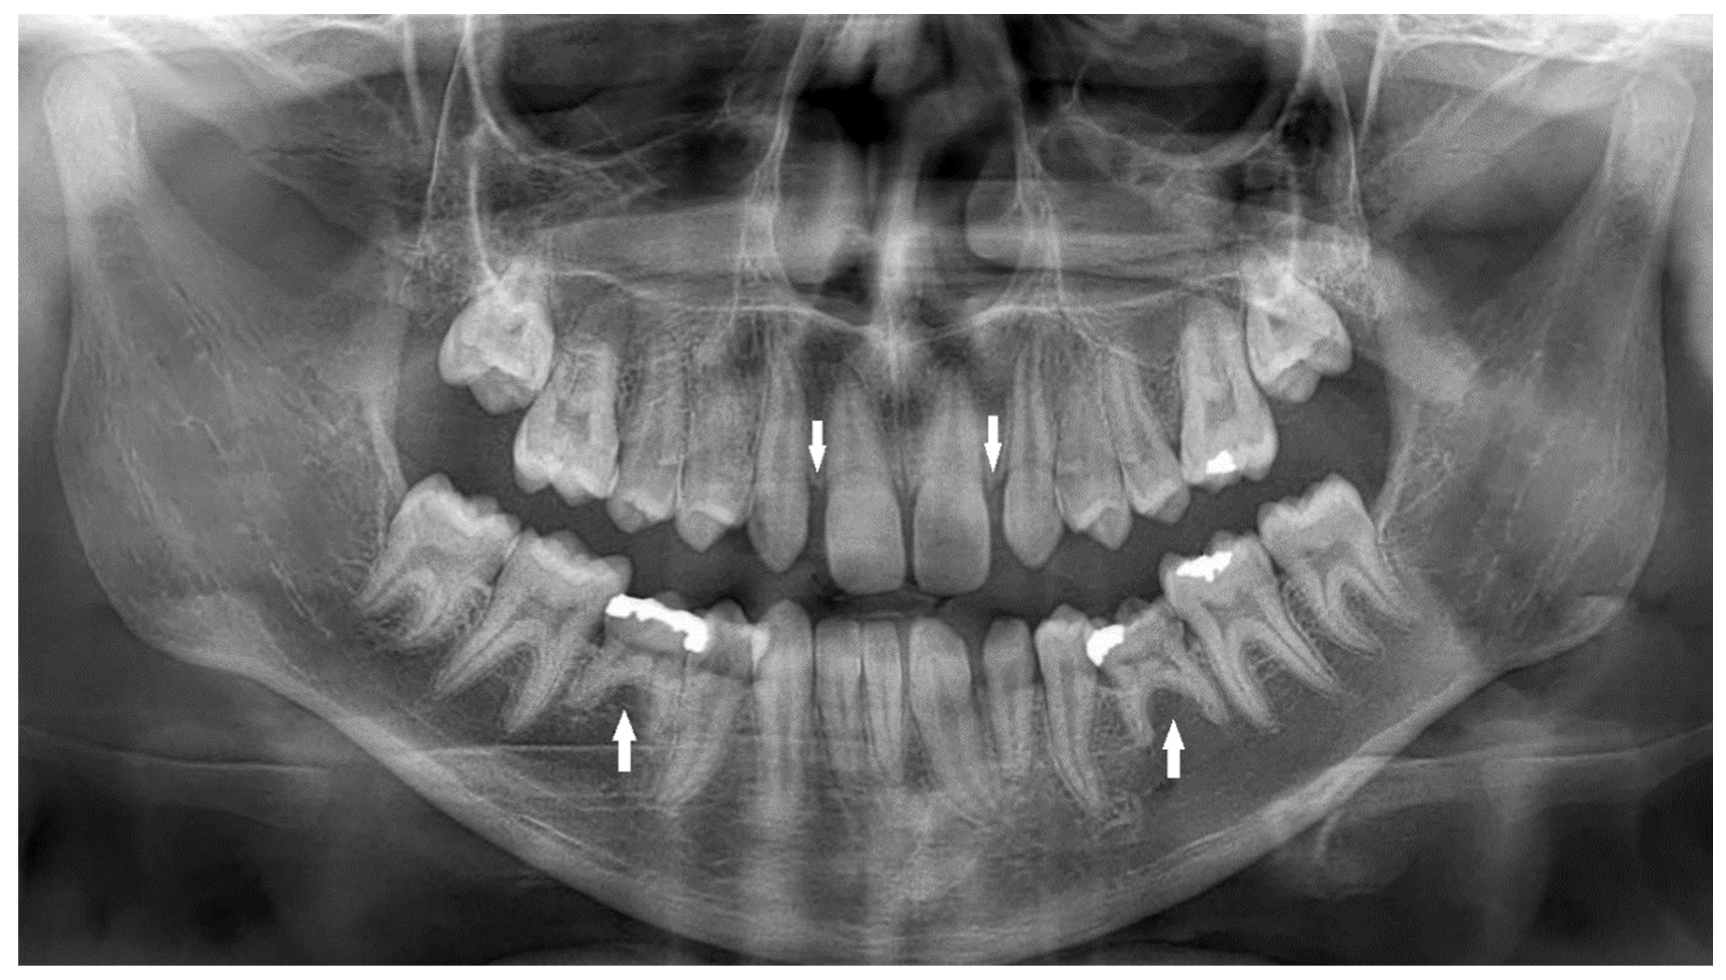

| Impaction | Failure of tooth eruption into the oral cavity. |

| Submergence | A primary tooth positioned under the occlusal surface of the adjacent teeth. |